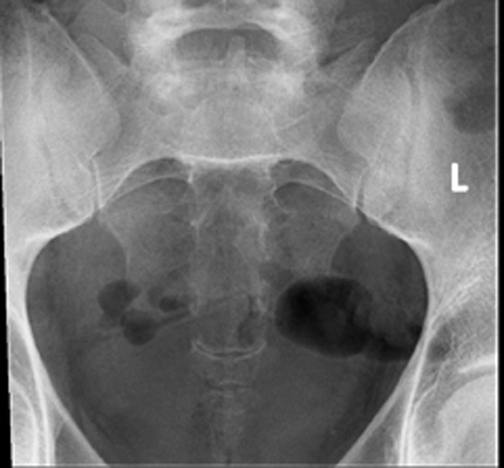

Identify parts of the sacrum and coccyx. Click the image for labeling.